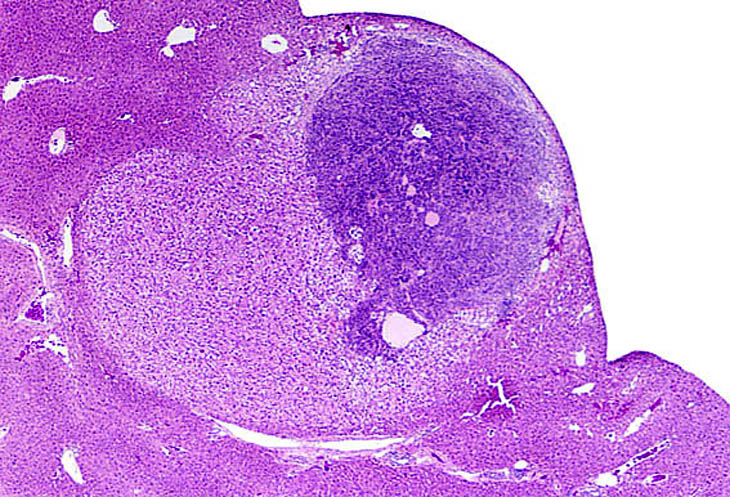

This small hepatoblastoma is present within an hepatocellular carcinoma.